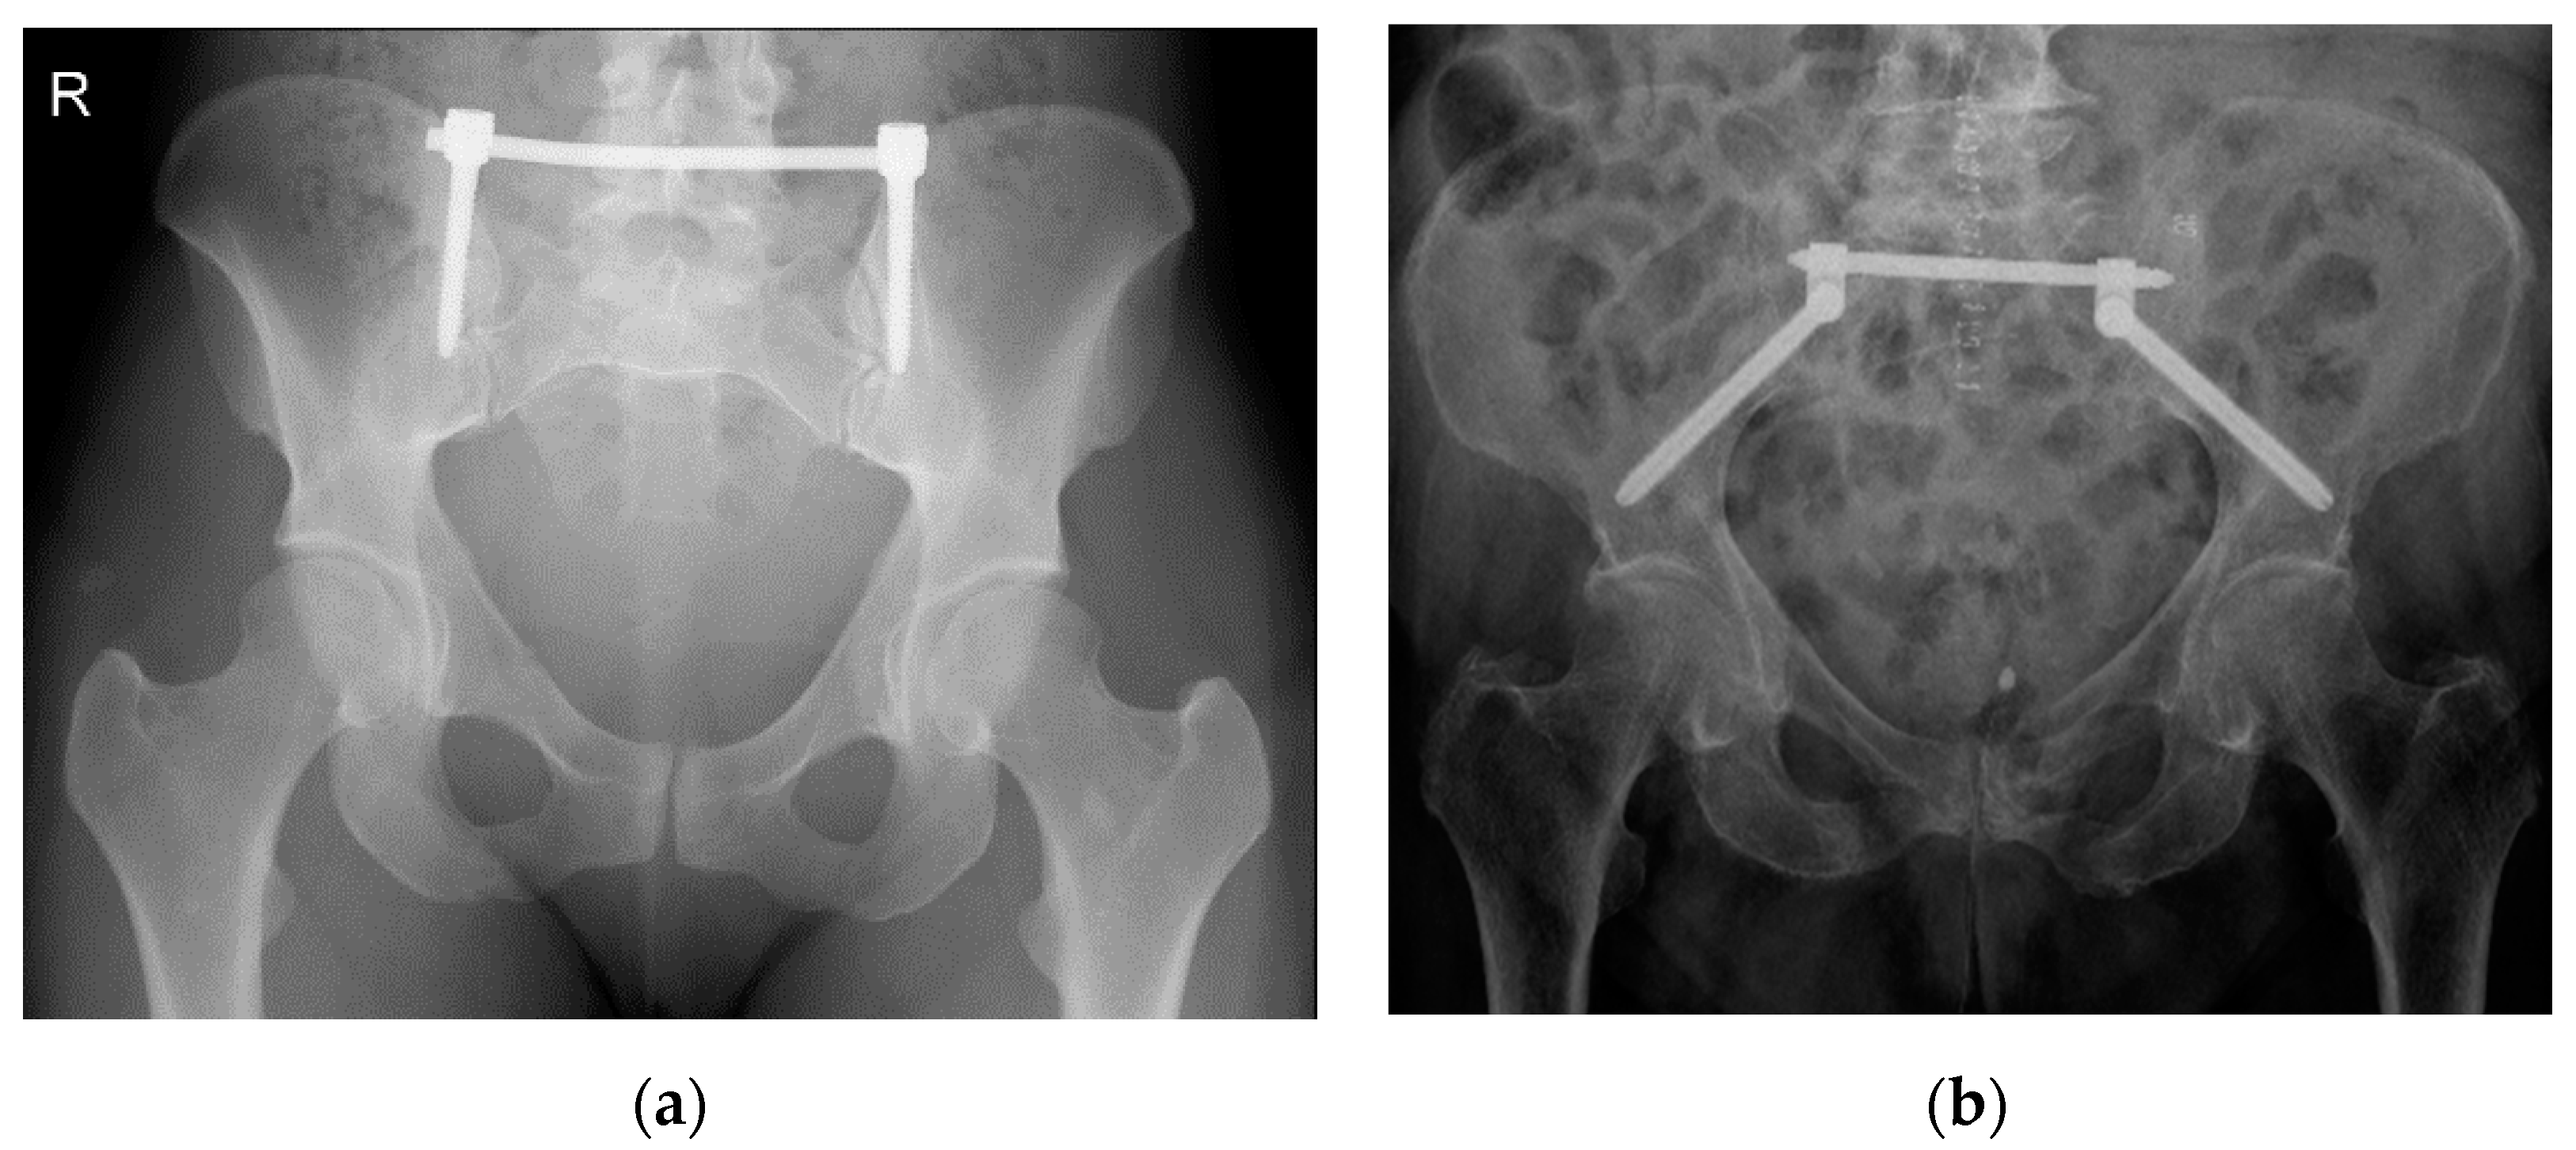

A minimally invasive procedure to stabilize an unstable posterior pelvic ring fracture is the transiliac internal fixation using an internal screw-rod system [9,10] (Figure 1). As described by Füchtmeier et al., a longitudinal incision of the skin and the fascia is performed 1 cm lateral and 2 cm above the posterior superior iliac spine. After that, the iliac crest is perforated by a pedicle finder and an ilium screw with a diameter of 7 mm and a length of up to 60 mm can be inserted in cranio-caudal direction parallel to the posterior gluteal line [9].

Figure 1.

X-ray of a transiliac internal fixator (TIFI)-osteosynthesis in cranio-caudal (a) and dorso-ventral (b) orientation.